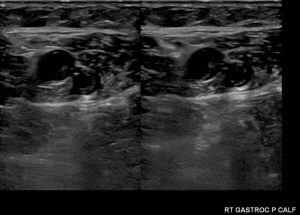

The diagnosis of calf vein thrombosis is established with duplex ultrasound utilizing the same principles that are used in proximal deep vein thrombi. A thrombus is diagnosed if there is lack of compression and/or lack of augmentation of flow. Also if there is no flow in the vein it may suggest a thrombosis. Some vascular laboratories do not perform calf ultrasound routinely, while others do. It is a matter of debate whether or not calf duplex ultrasonography is an accurate method to detect thrombi, however it has been published that a high standard laboratory can establish a low rate of clinically significant missed diagnoses.

An interesting fact is that calf vein thrombosis usually occurs in the gastrocnemius or soleus muscle veins or in the posterior tibial or peroneal veins. It rarely occurs in the anterior tibial veins. Duplex ultrasound which cannot visualize the anterior tibial vein appropriately is actually quite useful for the culprit veins outlined.